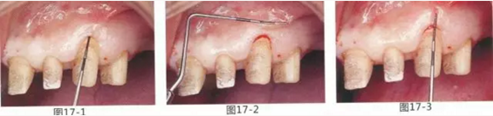

圖17-1~3 左上3的牙周袋探測值為3mm,角化牙齦寬度為2mm。也就是完全不存在附著齦,如果這種狀態(tài)下佩戴修復體的話,很有可能發(fā)生頸部暴露等問題。

圖17-4 左上1,2進行齦瓣根尖側(cè)轉(zhuǎn)移,左上3,4進行游離牙齦移植,在去除牙周袋的同時獲取附著齦。

圖17-5 牙周治療完成后的正面照。左上3,4部位處游離齦移植片的上端通過骨膜縫合固定在頰側(cè)嵴頂部。這樣可以使其愈合效果與齦瓣根尖側(cè)轉(zhuǎn)移相同。